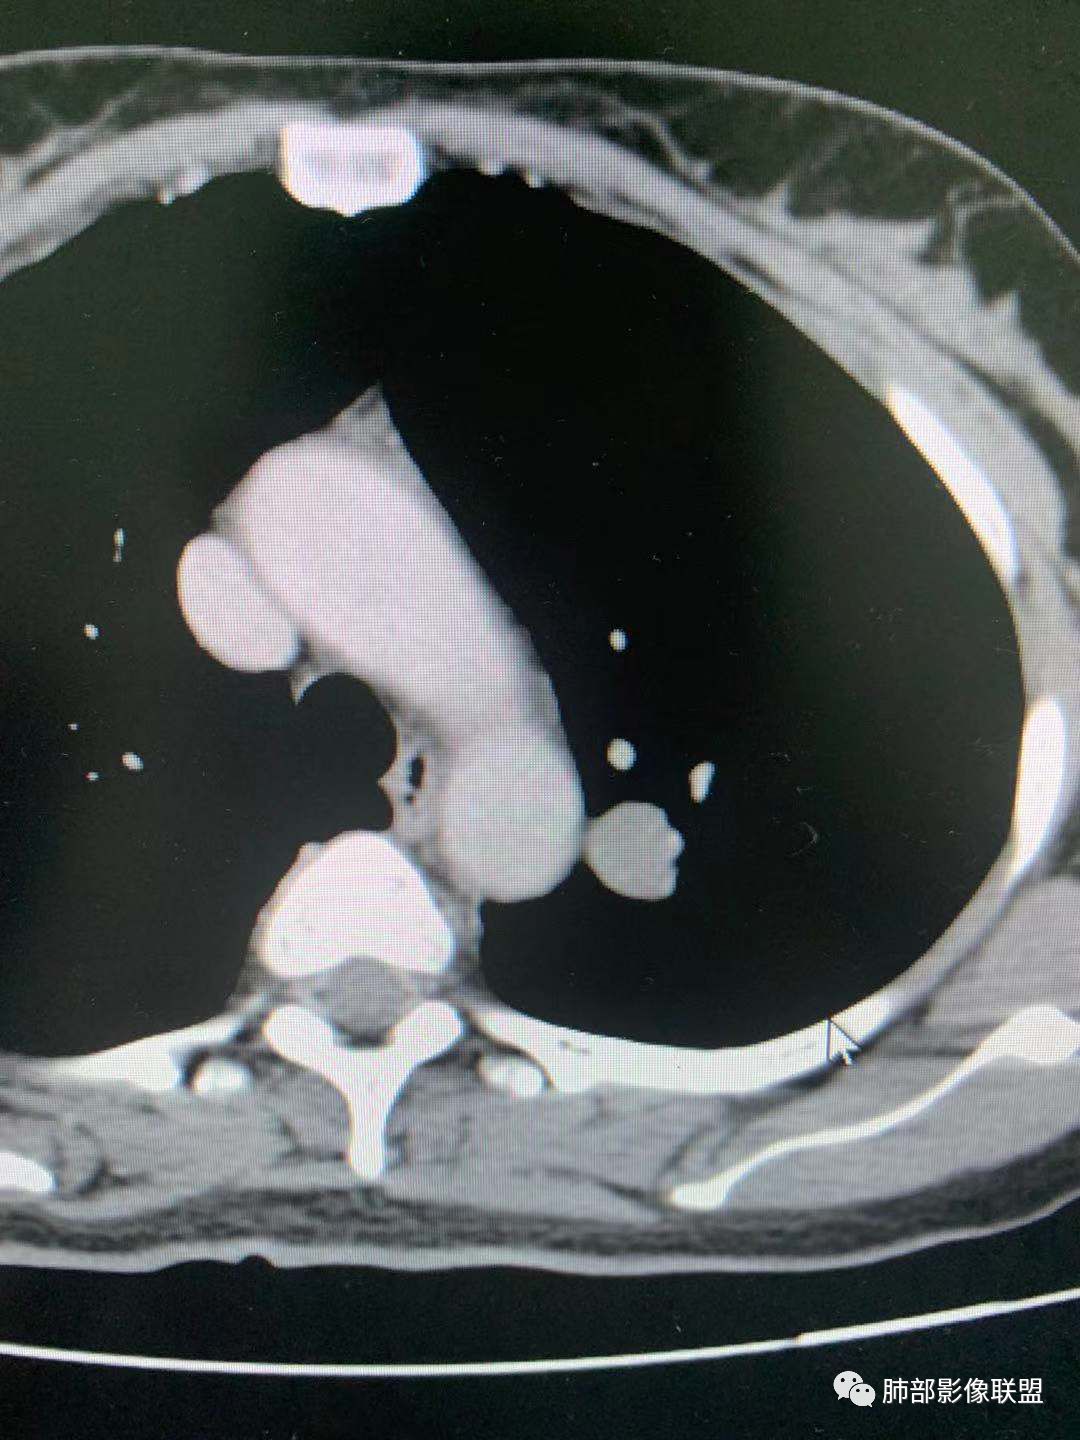

四、

这个怎么分析?

大家都考虑PSP?理由?

腺癌吧

有棘状突起,强化渐进性,强化了四十左右

导管冯

隐球菌?

凝睦

周围有边界清楚磨玻璃密度,腺癌

南边

CT值30HU;增强后:41/76HU

强化幅度:46HU

蓝天白云

周围有边界清楚磨玻璃晕

无胸膜牵拉

收缩力弱

1、边界清不清?

我觉得不清楚

有血管进入,清

边缘平直,延迟强化,血管贴边,支气管推移,毛刺较软,收缩力较弱。

血管贴边

大部分清,有小部分模糊

最上部层面,血管杂乱无章

增粗扭曲

2、形态规则吗?

边缘粗毛刺

类圆形

规则

如果这样,大家下一步应该观察啥?

旁边支气管倒是好像没有明显变窄。倾向于惰性腺癌,需要与psp鉴别

与支气管关系

长毛刺

啥关系啊?

从边绕过

支气管靠外侧,无明显变窄

好像是挤压,最好做重建

图不足啊,需要补充

这两条交代清楚了

这一条?

走形自然,无变窄,无明显侵犯

堵了?还是边上走了?

没堵

堵了是如何堵的?

我想提个上图一个疑问,为啥这靠内侧支气管的管径,比外侧支气管还窄?

你看血管啊

伴行

外侧伴行的血管大啊

提示它是级别更高的支气管啊

如果支气管堵了,考虑PSP几率就很小

所以我需要补充这个的重建

看清楚这条支气管

还是有收缩力

周围GGO不均匀,边界偏清

是的,有胸膜凹陷

姚鹏

mia

可能我的习惯不一样

我比较看重支气管

我认为有粗大短毛刺,我之前说成了棘状突了

有可能都是腺,时期不同

大结节的支气管应该堵了

远端没看到走出来

潘老师分析细致入微👍,各位老师也很厉害,提供这个病例的初衷主要是这个大的结节,结节周围边界清楚的GGO,部分边缘毛糙,和支气管关系不大,但还是有不踏实的地方,不要轻易诊断良性。另外肺内多发磨玻璃结节,有的胸膜牵拉,当时是建议随访观察,没想到群里老师都是火眼金睛